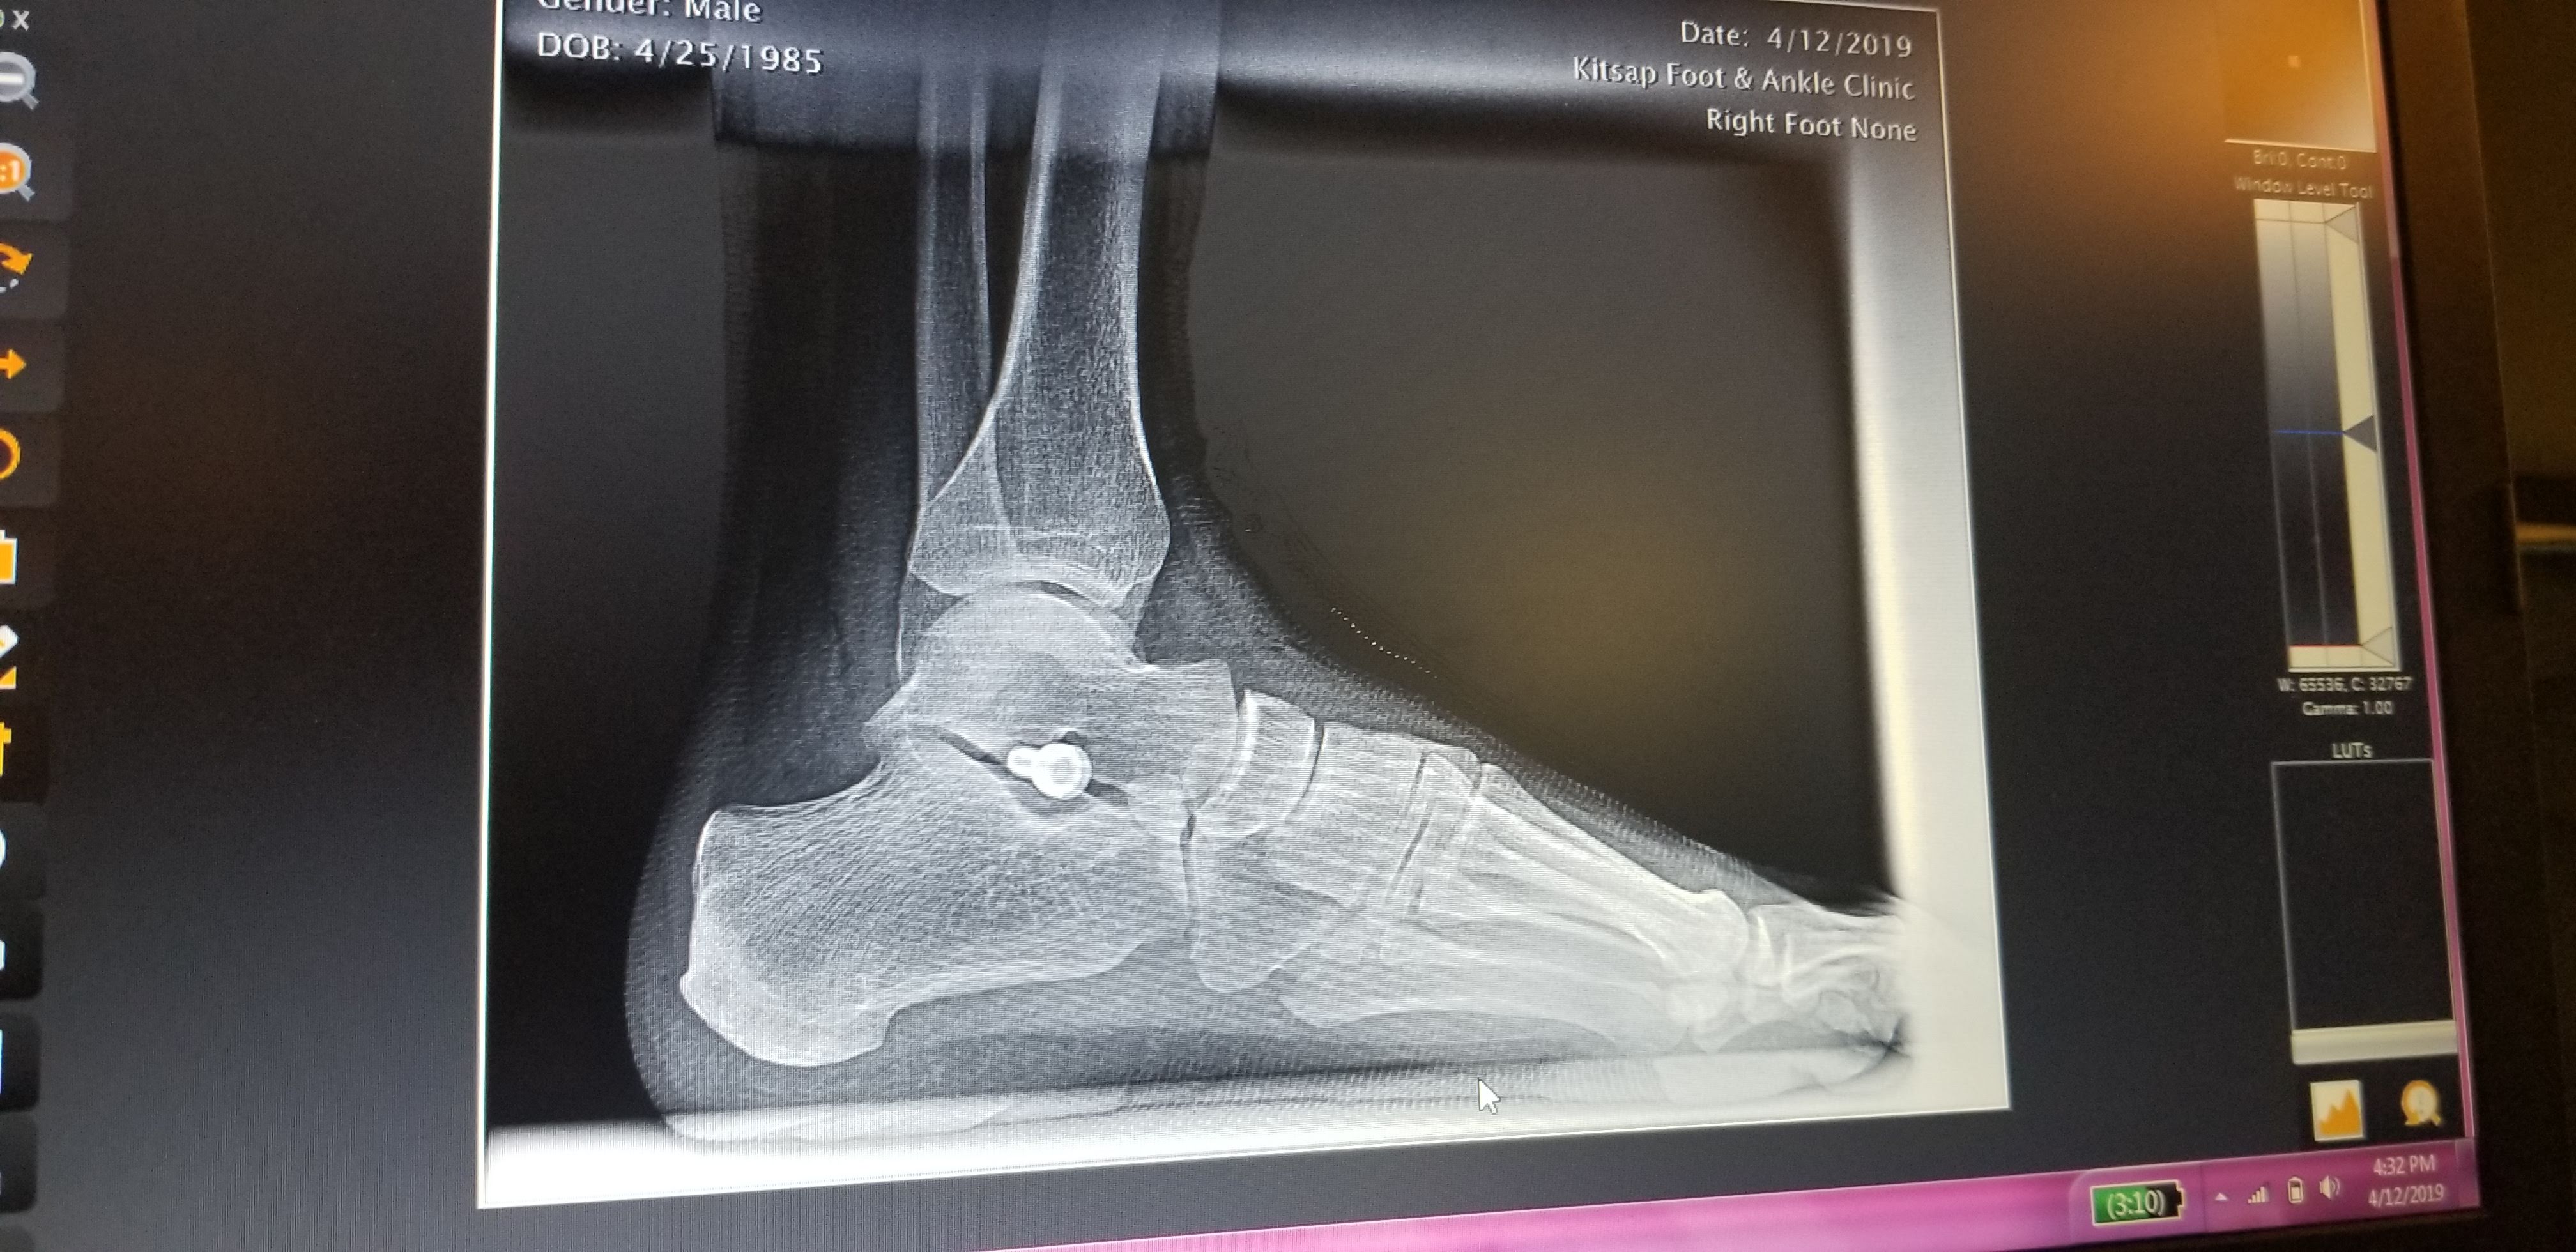

This time, the doctor did a bit more cutting and was then able to drive the implant deeper into the cavity between the talus and calcaneus bones. Preliminary X-rays showed good placement, so he stitched me back up. We then took X-rays with me standing on the freshly-repaired foot which clearly show that the implant is now much deeper than the first attempt from December.